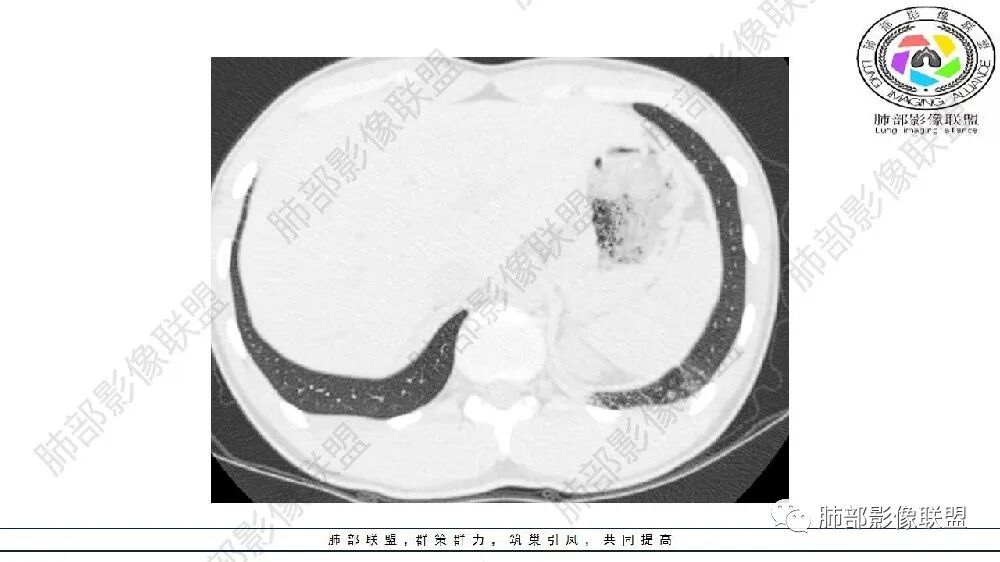

左肺下叶病变气体潴留,血管增粗,体积缩小,慢性炎遗留表现,考虑局部反复感染,气道通畅,考虑血管病变,肺静脉畸形,肺隔离症?

左肺下叶多发囊腔、斑片、索条(粗大扭曲的血管?)降主动脉左侧有血管影?首先考虑肺隔离症,建议增强扫描,鉴别囊腺瘤样畸形

年轻男性,左肺下叶肺动脉明显增粗特点(与对侧比较,降主动脉旁胸膜下分布粗大血管征、左肺下叶肺气囊腔和磨玻璃影,首选肺隔离征,与血管畸形鉴别,病理生理特点:体循环异常分支(压力高)与左肺下叶肺动脉成异常交通。血管血流倒灌左肺下叶表现。

连续的看这些管状影与肺动脉好像没有连续性,不知道是否与主动脉相连,附近高密度影,提示感染。

可见囊状影、管状影,附近血管明显增粗,似乎与肺动脉不相连

1、需要明确血管与主动脉关系,如果相连--隔离症

主要观察左下叶病灶,应该是做过手术或明确了血管与主动脉关系,就目前的表现而言还是更支持隔离:肺动脉、支气管分支似乎没进入病灶区,这是隔离或体动脉供血的特点。囊腺瘤样畸形,按理肺动脉及支气管照样进入这个区域才对;需要重建观察这些血管、支气管才好明确